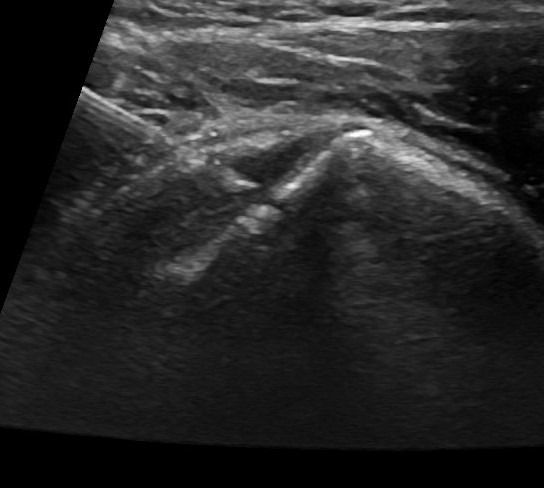

Η τεχνική PRP περιλαμβάνει τη λήψη μίας μικρής ποσότητας αίματος του ασθενούς, το οποίο φυγοκεντρείται ώστε να διαχωριστεί το πλάσμα που είναι πλούσιο σε αιμοπετάλια. Το προκύπτον πλάσμα εγχέεται, με την καθοδήγηση υπερήχου, στο σημείο της βλάβης.

Η καθοδήγηση υπερήχου κατά την ενέσιμη θεραπεία PRP αποτελεί κρίσιμο παράγοντα για την ακρίβεια και ασφάλεια της διαδικασίας.

Με τη δυνατότητα παρακολούθησης της βελόνας σε πραγματικό χρόνο, εξειδικευμένος Ιατρός-Ακτινολόγος μπορούν να καθορίσει με απόλυτη ακρίβεια την περιοχή όπου πρέπει να γίνει η ένεση. Αυτό εξασφαλίζει ότι η εισαγωγή του PRP θα γίνει ακριβώς στην επιθυμητή θέση, αποφεύγοντας γύρω ιστούς, νεύρα και αιμοφόρα αγγεία.

Η χρήση της υπερηχογραφίας όχι μόνο μειώνει τον κίνδυνο επιπλοκών, αλλά βελτιώνει και τα αποτελέσματα της θεραπείας, καθώς η ένεση διενεργείται με ακρίβεια στην πάσχουσα περιοχή, και όχι κατά προσέγγιση.